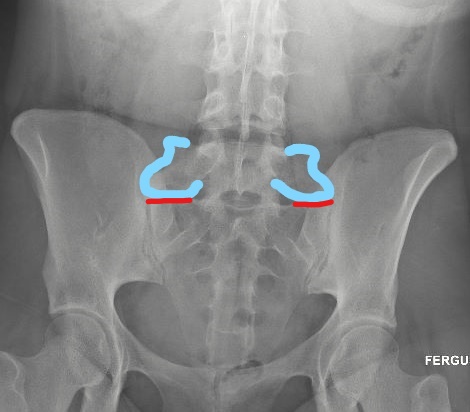

On the below radiograph of the pelvis, the enlarged

transverse processes are outlined in blue.

Below, the red lines demonstrate the abnormal articulation

between the Bertolotti’s and the sacrum, which is the area which is causing

pain.